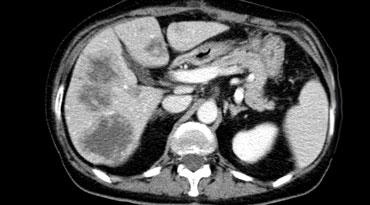

Di căn giảm mạch biểu hiện là các tổn thương giảm tỷ trọng trong thì tĩnh mạch cửa muộn. Lưu ý có một số ngấm thuốc dạng viền ở vùng ngoại vi còn sống của các ổ di căn.

Thì tĩnh mạch cửa

Chụp thì tĩnh mạch cửa dựa trên nguyên lý ngược lại.

Chúng ta chụp gan khi gan đã được nạp đầy thuốc cản quang qua tĩnh mạch cửa để phát hiện các khối u giảm mạch (hình).

Thời điểm tốt nhất để bắt đầu chụp là khoảng 75 giây, đây là thì tĩnh mạch cửa muộn, vì sự ngấm thuốc của tĩnh mạch cửa đã bắt đầu từ 35 giây trong thì động mạch muộn.

Thì tĩnh mạch cửa muộn này còn được gọi là thì gan vì lúc này các tĩnh mạch gan đã phải ngấm thuốc.